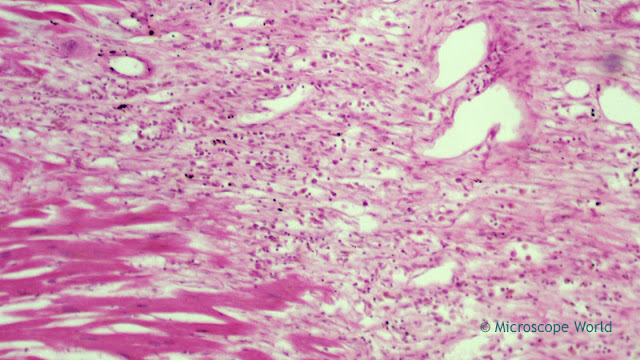

The images below are of myocardial infarction (a heart that has been through a heart attack) and were captured using a clinical lab microscope and an HD microscopy camera.

Microscopy image of a heart attack (myocardial infarction) under the microscope at 400x.

Myocardial infarction (heart attack) under the microscope at 400x.